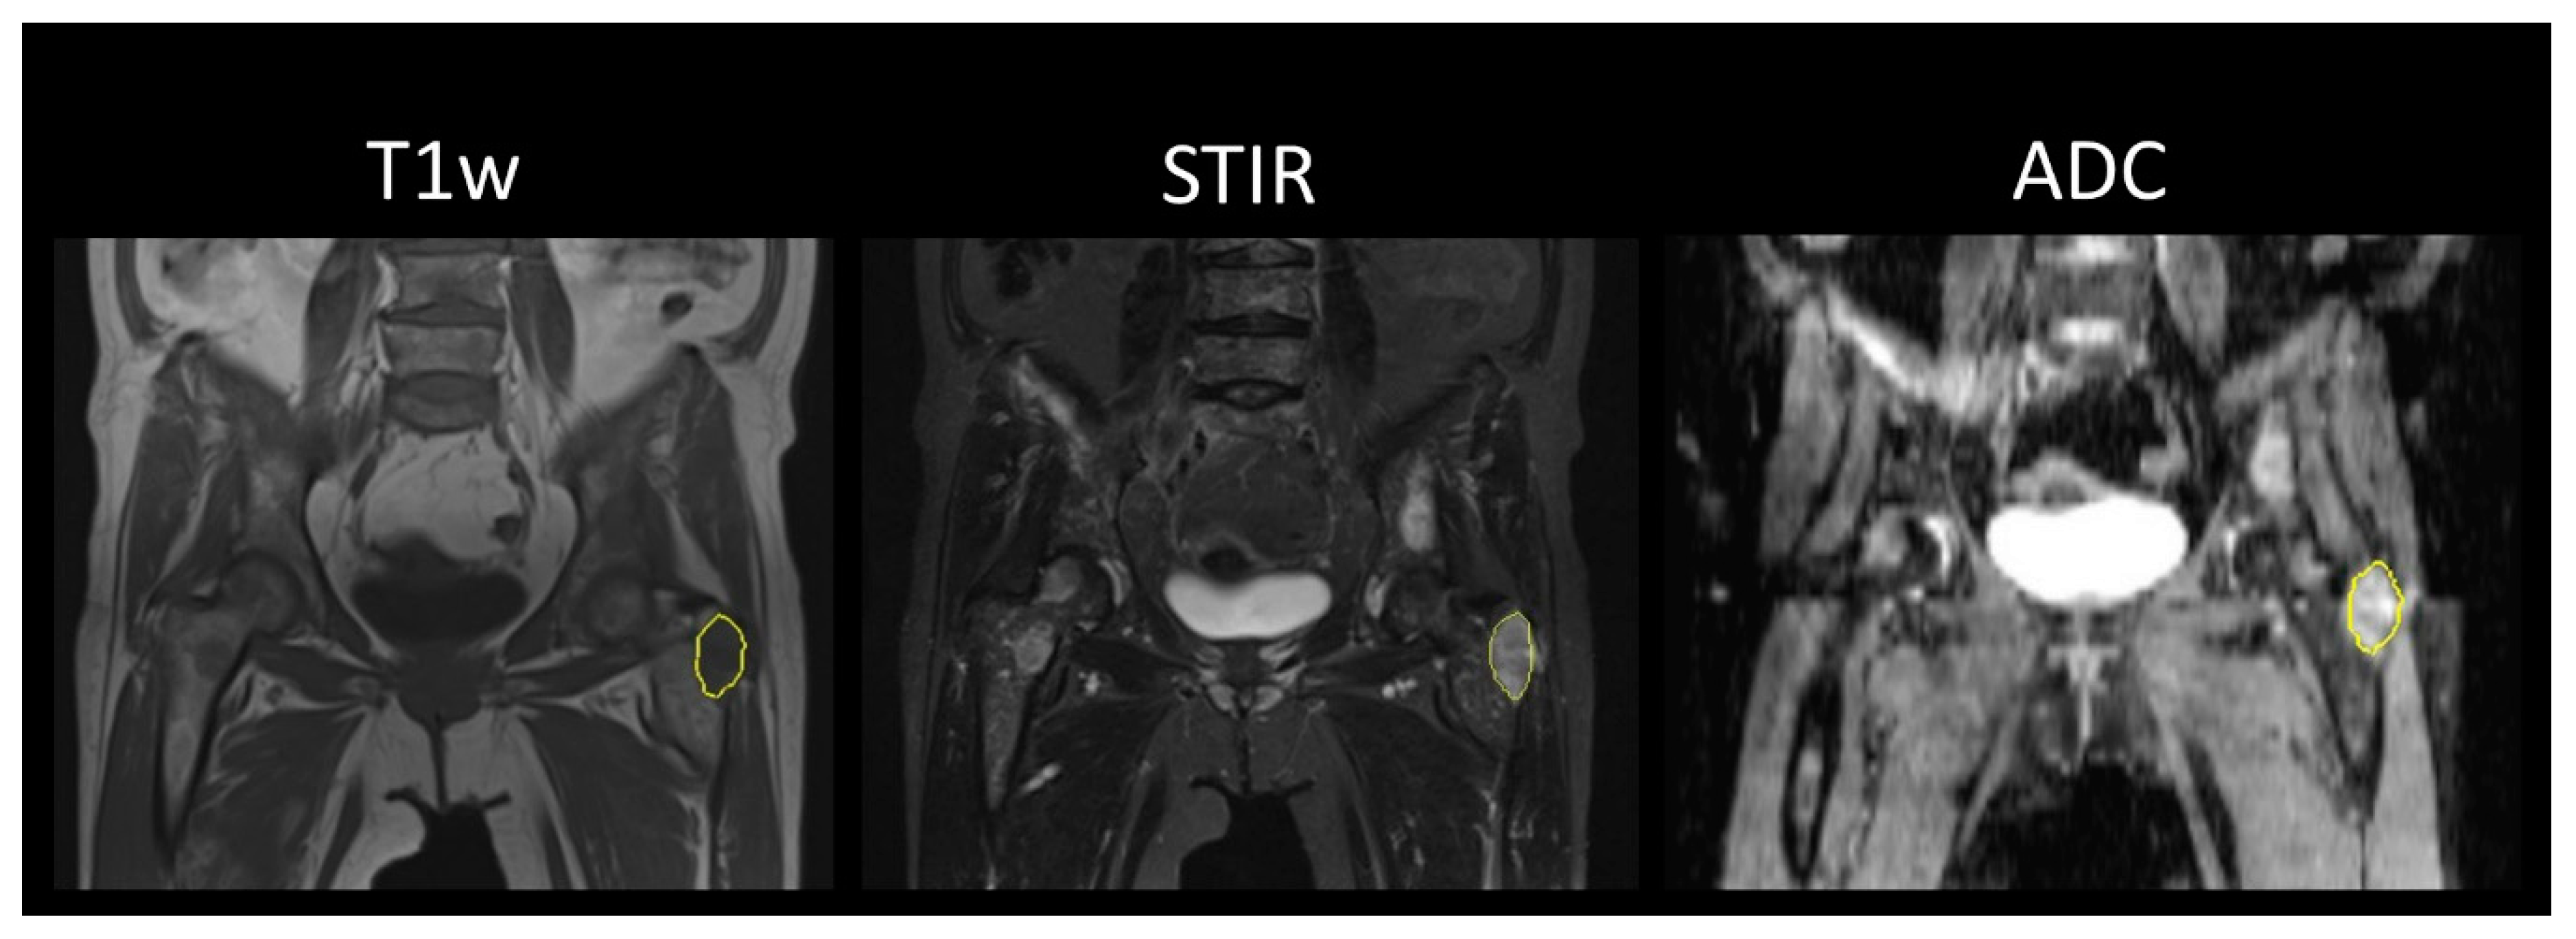

2.3. Image Analysis